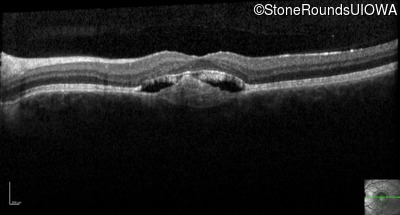

Optical Coherence Tomography - Left - 20/20 -3

Exemplar / OCT Stack